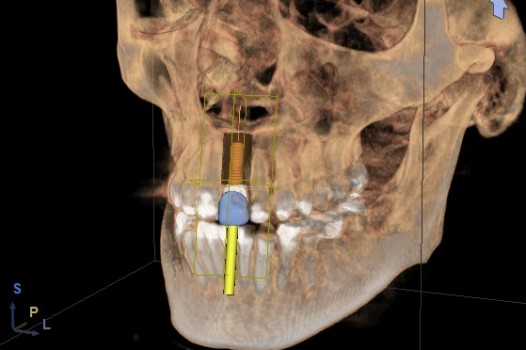

With 3D CBCT X-ray imaging, Dr. Klim can capture highly detailed, three-dimensional views of the teeth, jawbone, nerves, and surrounding structures. Using this data, advanced software allows Dr. Klim to virtually plan dental implant placement with exceptional precision.

Once the digital planning phase is complete, the information is sent to a dental laboratory or an in-office milling system. From this plan, a custom surgical guide (also called a stent) is fabricated specifically for the patient.

During the procedure, the guide is placed securely in the patient’s mouth. The guide’s precise opening directs the instruments, allowing the bone to be prepared and the implant to be placed in the exact planned position, improving accuracy, safety, and long-term results.

Implant CBCT Imaging

Virtual restorative and implant planning prior to removal of fractured root.  Plans are made for precise implant placement using 3D CBCT imaging, Sirona Omnicam Scan and fabrication of a guided implant placement appliance.